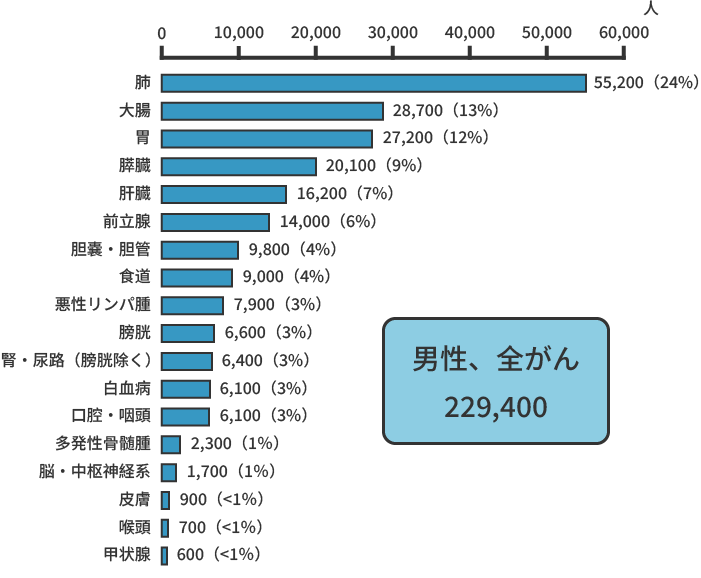

また、同じく2021年のデータによると、がんによる死亡者の数は、約37万8,600人(男性約21万8,900人、女性約15万9,700人)と推計されています。部位別でみると、男性では肺がん(24%)が最も多く、次いで大腸がん(13%)、胃がん(12%)、膵臓がん(8%)、肝臓がん(7%)の順、女性では大腸がん(16%)が最も多く、肺がん(14%)、膵臓がん(12%)、乳がん(10%)、胃がん(9%)と続きます。

部位別のがん死亡者数(2020年)